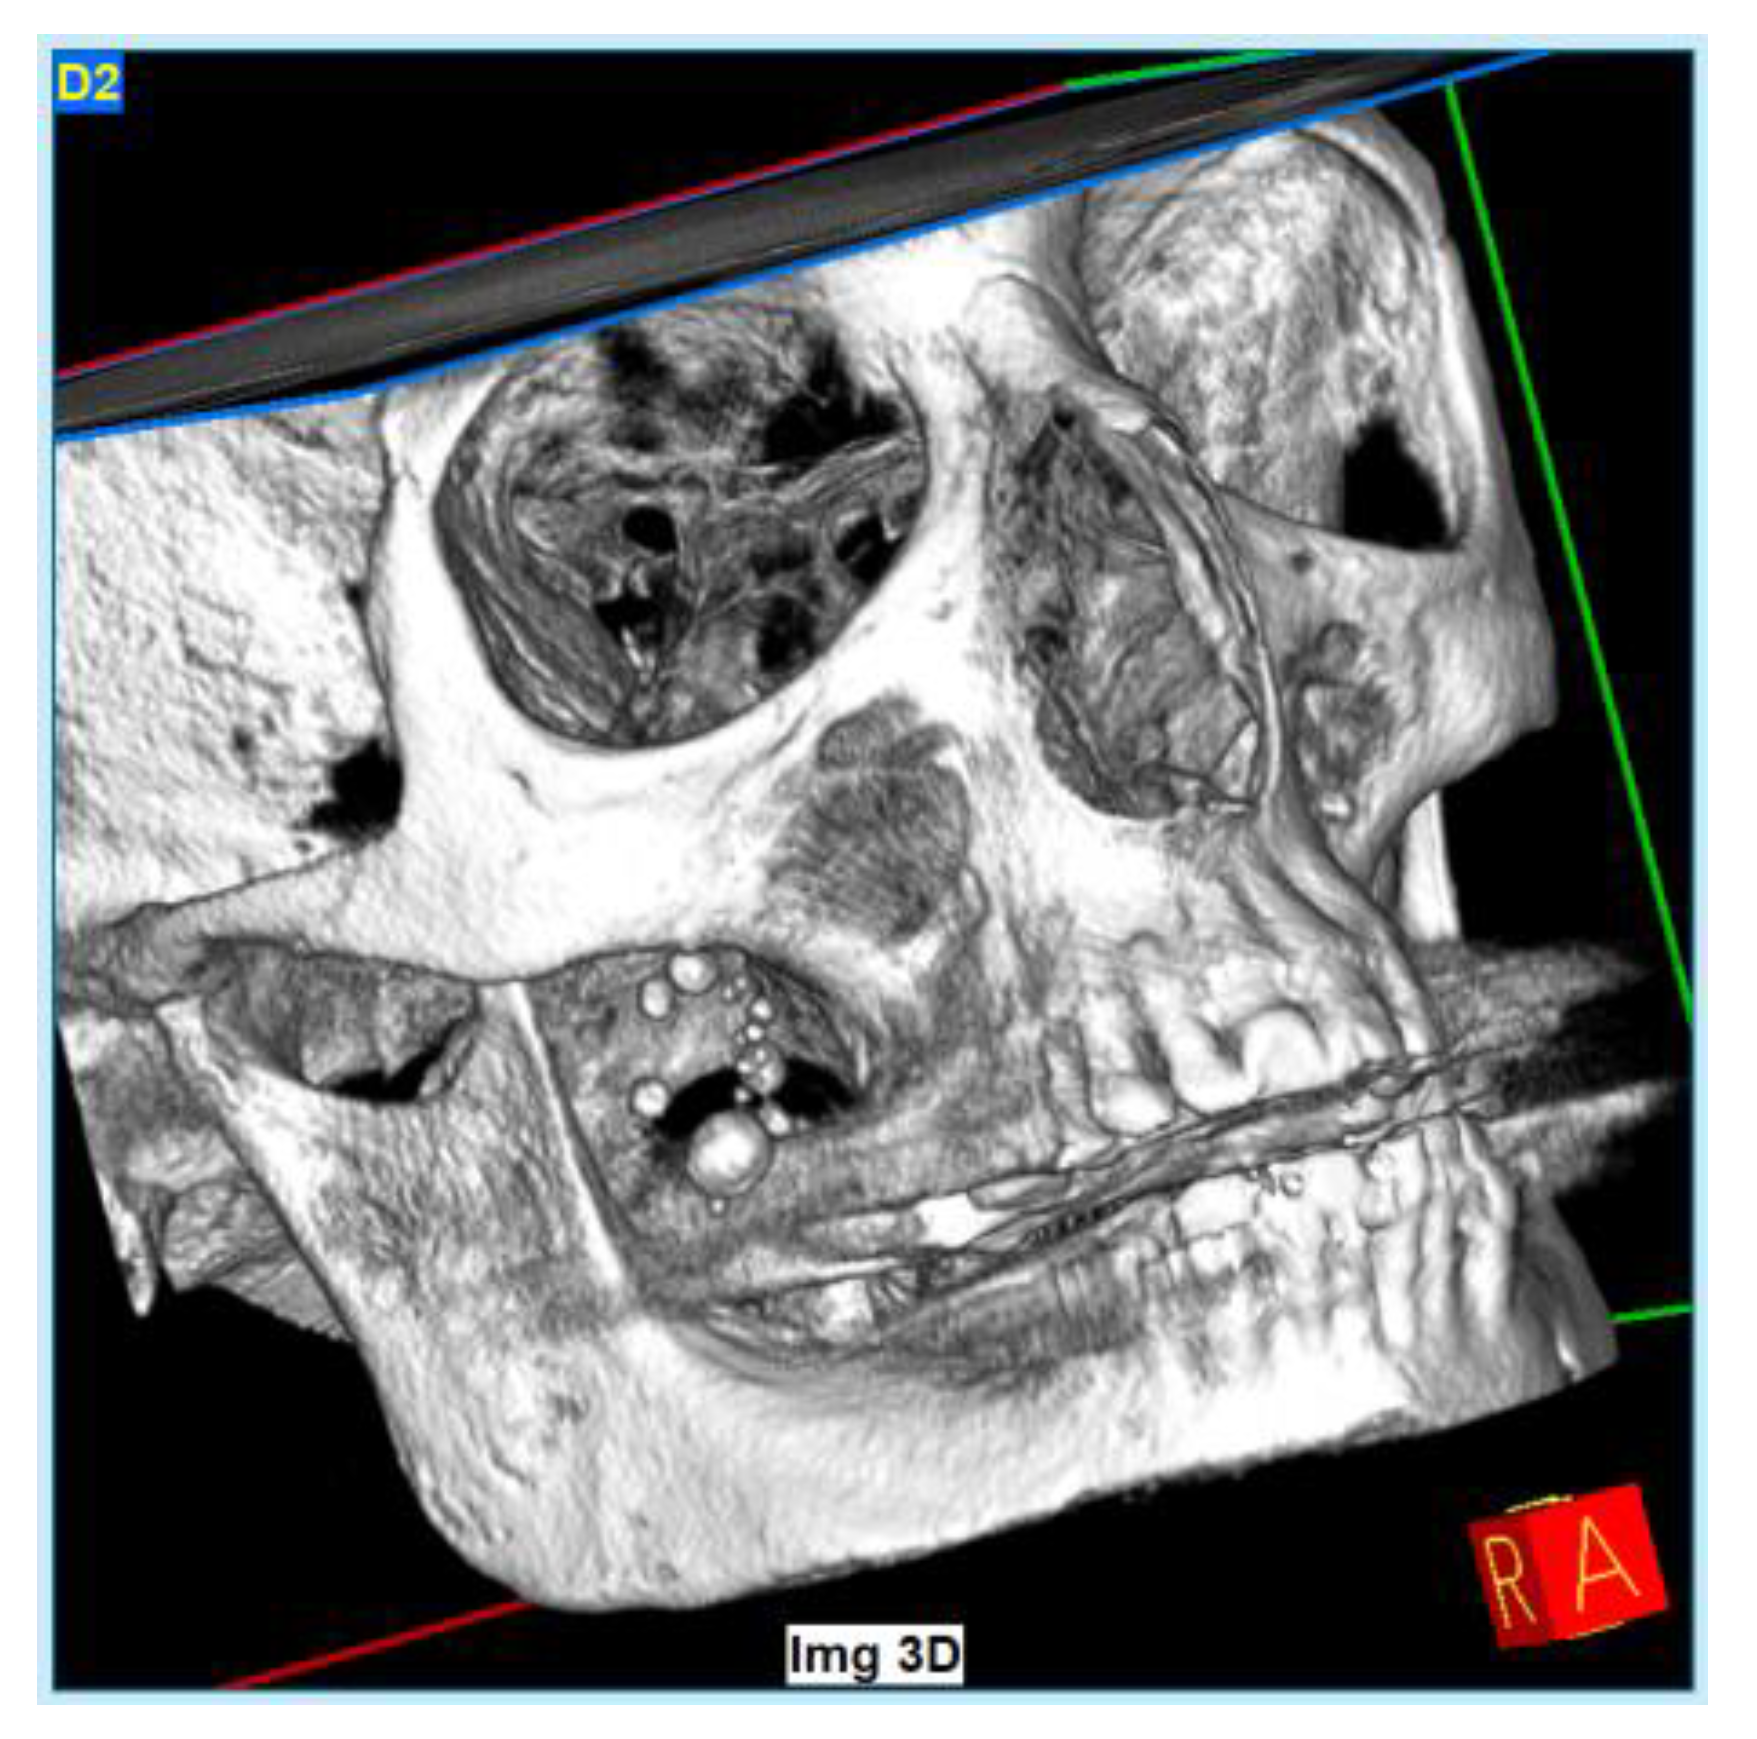

2. Case Presentation